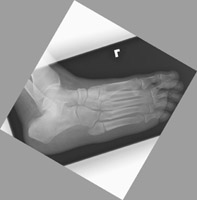

- Click on the image for a larger versionBOblique radiograph of the foot. Two years later the patient returns for continued pain. A radiograph reveals nonunion of the fracture, a frequent complication of the Jones fracture.